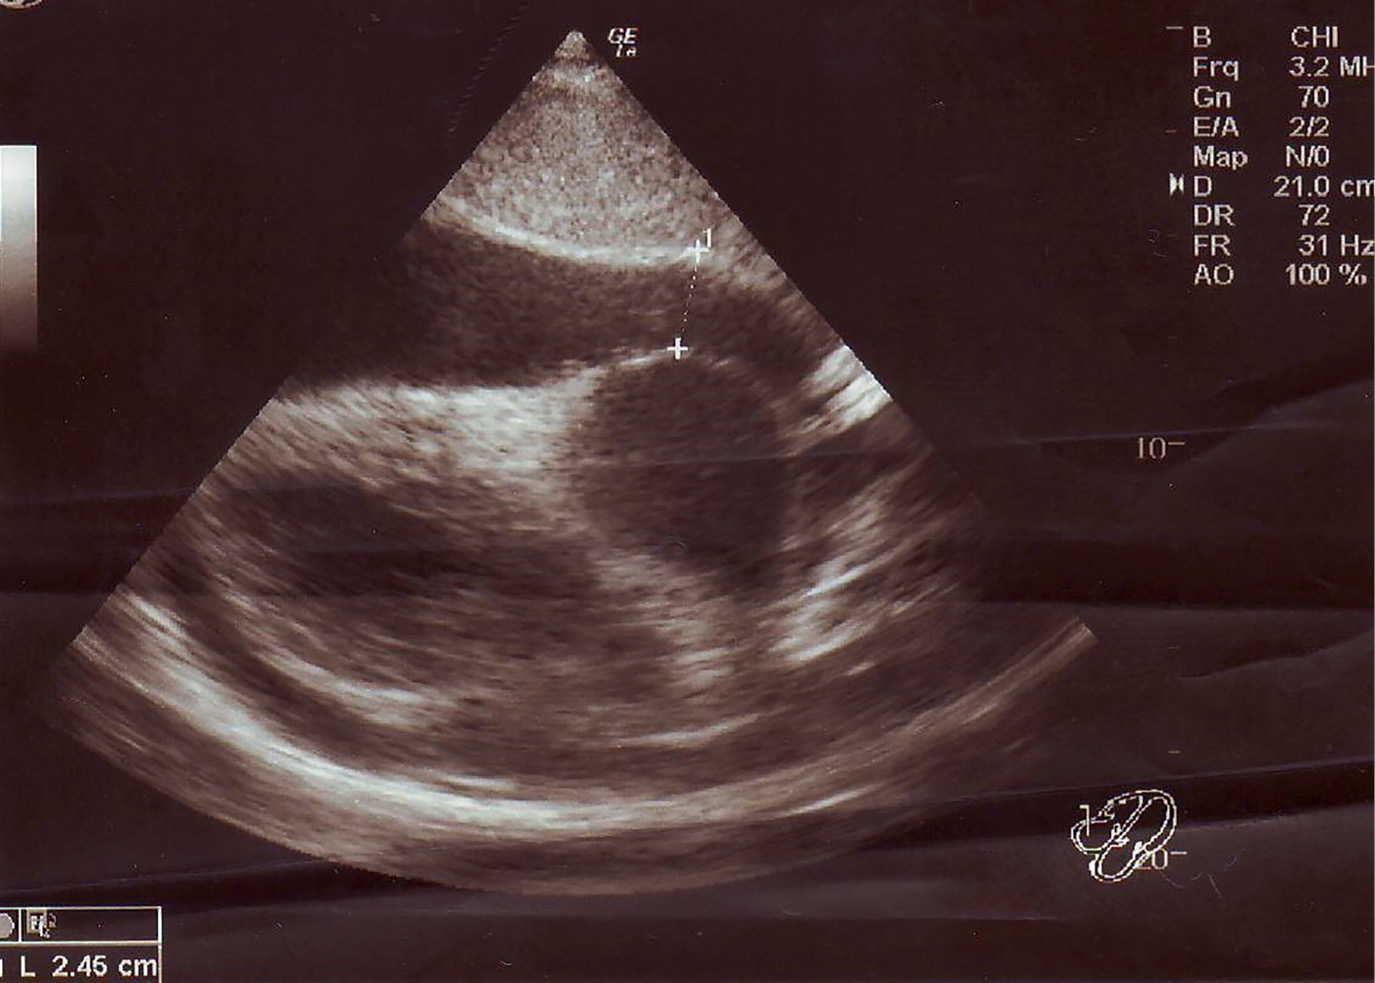

4. Рисунок 4. УЗИ сердца. Гидроперикард за правыми отделами сердца. | |

Тема | ||

Тип | Исследовательские инструменты | |

Посмотреть

(205KB)

|

Метаданные ▾ |